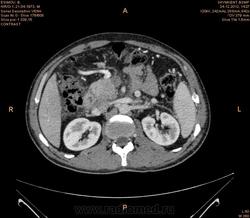

Предварительно образование головки ПЖ, и в печени. Что с ферментами?

на операций рак головки подж.железы с метастазир. печень.

инфильтрация тут нисходящей 12 перст кишки , расширенного холедох,расширенный вирсунгов проток ,нижная граница очень близко прилежит к нижней полой вене с правой почечной веной ,но четко визуализирутся передний листок фасции Героты(нельзя исключить ее инфильтрацию), инфильтрация конгломератом увеличенных лимфатических узлов ворот печени портальной вены с варикозным расширением вен, на вышележащий срезах четко определяются верхняя брыжеечная вена и артерия ,не хватает срезов для полной визуализации(помогли бы мпр),инфильтрирована восходящая ободочная кишка,конгломерат лимфат узлов за головкой поджелудочной железы в виде гиподенсивного участка вытянутой формы , ,мтс в печень,парааортальные